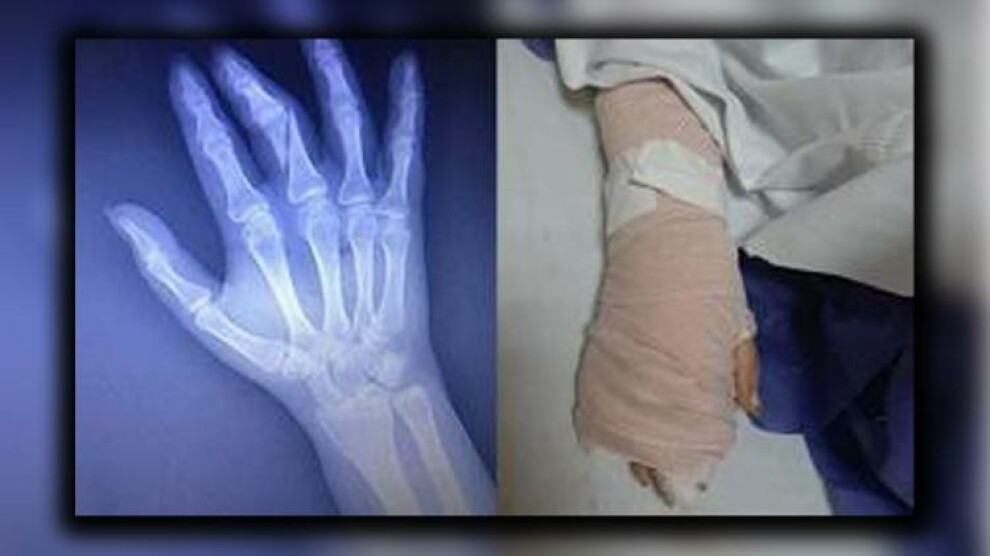

حراست از وی خواستە بود که همەی تصویربرداری‌ها و مصاحبه‌ها را حذف کند اما این خبرنگار از این کار امتناع کرده و در نهایت ماموران حراست با او درگیر شده‌اند درگیری و ضرب و شتم این خبرنگار باعث شد که انگشتان دستش بشکند.

وی در حال حاضر در بیمارستان به سر می‌برد و تحت عمل جراحی قرار گرفتە است.